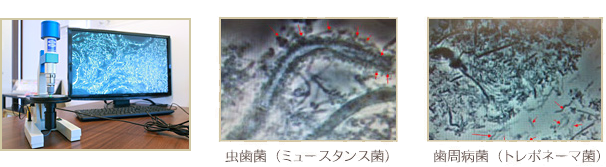

病原菌が発見できる位相差顕微鏡

レントゲンには細菌は映りません。だからこそ細菌を発見することが出来る位相差顕微鏡検査は重要なのです。虫歯や歯周病は虫歯菌、歯周病菌が原因による感染症。患者さまの虫歯・歯周病リスクが高い奥歯から少量の汚れを取り、その場で瞬時に検査が可能です。もちろん痛みは全くありませんから安心です。

画面を通じて患者さんごとに口腔内の細菌類の状況や変化を把握できますので、発症予防にも繋がりお口のリスク管理には最適です。別途料金はかかりませんのでご安心ください。